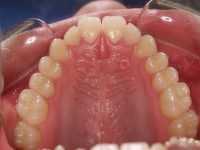

Chica de 17 años tratada en 1 año con stripping en los dientes inferiores

El stripping consiste en la reducción interproximal del esmalte entre los dientes posteriores y anteriores, así obtenemos espacio para alinear los dientes apiñados.